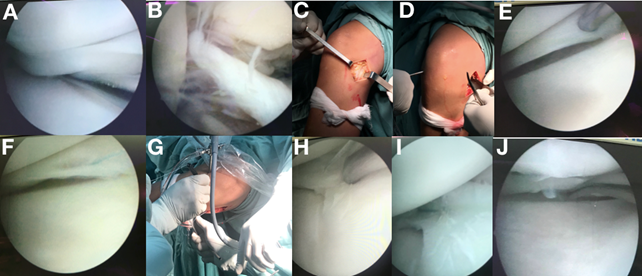

En sala de operaciones, con el paciente en decúbito dorsal bajo anestesia general, se colocó manguito neumático y un soporte para miembro inferior. Se realizaron los portales artroscópicos clásicos anteroexterno y anterointerno, visualizándose la lesión longitudinal del cuerno posterior del menisco interno y la rotura del LCA. Se procedió en primer lugar a la reparación meniscal. Una vez localizada la lesión, se testó la estabilidad del menisco con el probe, y se hizo un debridamiento con shaver del tejido fibroso. A continuación, se realizó un abordaje posteromedial mediante una incisión vertical en piel desde el tubérculo del aductor hasta el sector posterior del platillo tibial interno, sobrepasando 2cm la línea articular. En la disección profunda, se disecó la fascia del sartorio hasta observar el triángulo anatómico formado por: la cápsula (anterior), el gemelo interno (posterior) y el semimembranoso (inferior). Se llevó la rodilla a 20 grados de flexión y se colocó la cánula flexible en la cara superior de la lesión del menisco interno y usando material para pasar las suturas, se realizó la primera pasada de la aguja, recuperándose la misma con retractor posterior con la rodilla a 90 grados de flexión para evitar lesiones neurovasculares. Se prosiguió a la segunda pasada de la aguja en el sector de la lesión correspondiente, quedando ambos extremos del hilo por afuera, los cuales se anudaron. Se hicieron 2 puntos de sutura al menisco, comprobándose la estabilidad posterior a la reparación (Figura 2). A continuación, se pasó a realizar la plastia de LCA. Se realizó un debridamiento previo de los restos de LCA. Se amplió distalmente abordaje posteromedial, para exponer la inserción de los isquiosurales, y se obtuvo injerto de pata de ganso. Se observó huella del LCA a nivel del fémur, y se realizó el túnel de 8mm. A continuación se coloca guía para túnel tibial, realizándose el mismo. Se colocó el injerto y se fijó próximalmente con endobuttom, y distalmente con tornillo de interfrencia de titanio 7X20mm con la rodilla en flexión de 30 grados y realizándose cajón posterior (Figura 3). Se verificó la estabilidad anterior intraoperatoria, se realizó el cierre por planos y un vendaje elástico del miembro. Los controles se realizaron de la siguiente manera: a los 15 días, a las 6 semanas, a los 3 meses, a los 6 meses, al año y a los 2 años.

Figura 3. Imágenes del intraoperatorio de la plastia de LCA. A.Injerto de partes blandas (pata de ganso) utilizado. B y C. Colocación de la aguja de Kirschner (kw) guía para el túnel femoral. D. Imagen del túnel femoral. E. Posición de la guía para el túnel tibial. F. Mechado del túnel tibial. G. Resultado final con el injerto fijo y tenso (asterisco negro), y su relación con el ligamento cruzado posterior (flecha negra con borde blanco)